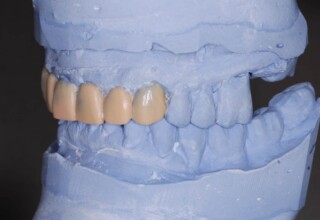

Porcelain Veneers

The best way to solve esthetic problems of the anterior teeth. They combine very little tooth grinding with very high esthetic performance. In the following extensive case anterior teeth presented with: old restorations, staining, poor shape, length and tooth –gingiva ratio. Meticulous diagnostic waxing was performed on study casts and temporary veneers were manufactured. Temporary veneers were used intraorally to evaluate the incorporated changes and to further modify and adjust were needed. When esthetics and function were approved by the patient and were satisfying for the operator the temporaries were used as a guide for the final porcelain veneers. The five final veneers on the upper anterior teeth restored the smile of the patient to almost perfection.

Initial appearance

Final appearance